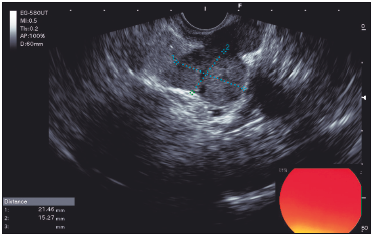

Se realizó una colonoscopía que identificó una lesión subepitelial rectal. La USE subsiguiente reveló una lesión subepitelial en el recto medio-inferior, de aproximadamente 10 mm x 15 mm, originada en la cuarta capa ecogénica (muscular propia), continua con una formación nodular mesorrectal de 21 mm x 15 mm. También se observaron ganglios linfáticos mesorrectales regionales de 5 mm a 6 mm (Figura 1 y 2).

Figura 2. Formación subepitelial de 10 x 15 mm continua con lesión nodular de 21 x 15

mm en mesorrecto